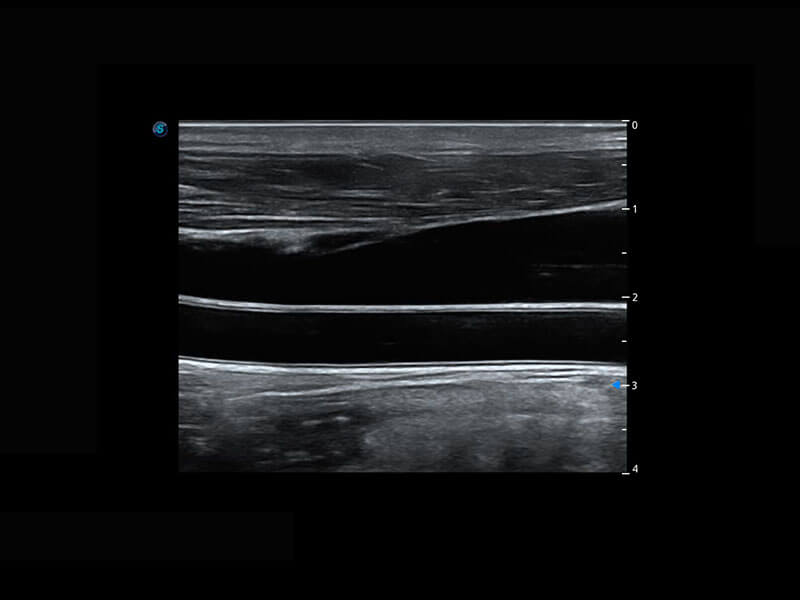

P60搭載寬頻帶線陣探頭、寬景成像、彈性成像技術(shù),為您提供乳腺應(yīng)用方案。P60支持高頻相控陣探頭、線陣探頭、腹部高頻探頭、腹部微凸探頭等,豐富的探頭群搭載敏感的彩色血流成像,適用于新生兒多種臟器檢測要求,滿足新生兒篩查需求。

新生兒脊髓圓錐